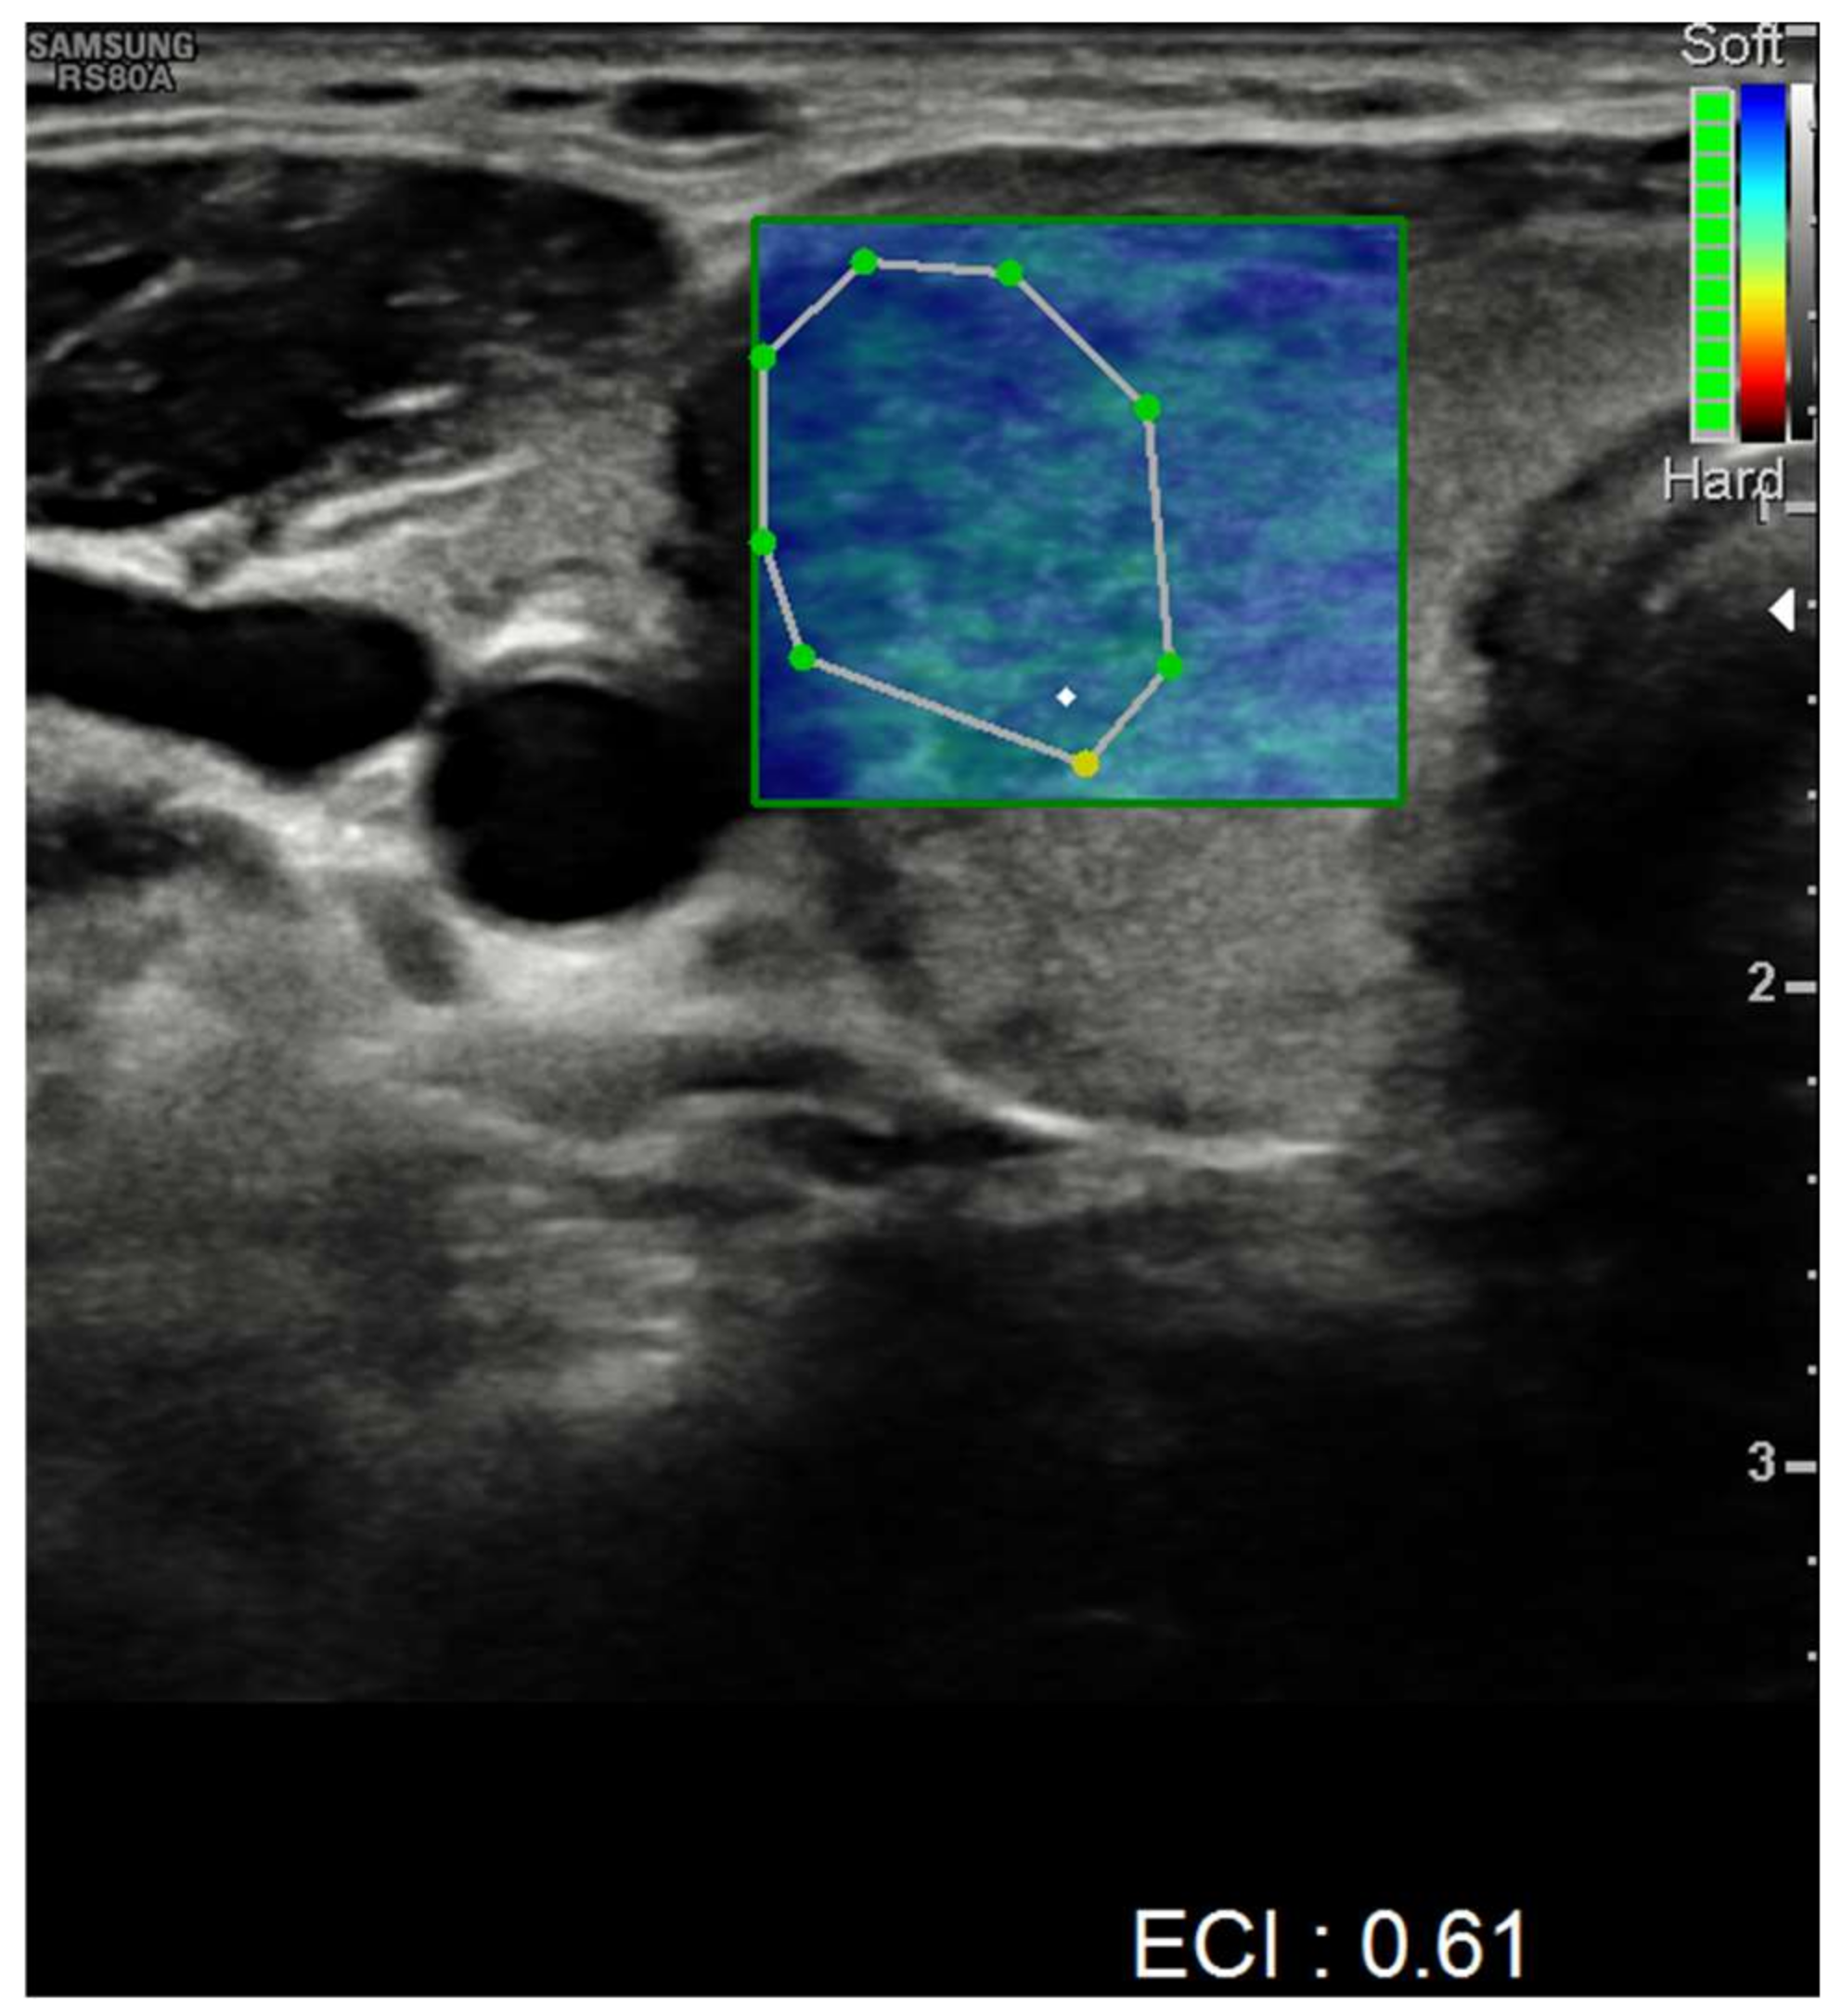

| Ultrasound findings at presentation | Asymmetric thyroid enlargement with two hypoechoic areas with no internal vascularity on right thyroid lobe | Diffuse thyroid enlargement with hypoechoic areas with heterogeneous echotexture and no evidence of increased vascularity | Diffuse enlargement of thyroid gland with hypoechoic nodules with hyperechoic shoots (micronodular pattern) without increase in vascularity | ||||||||||||||